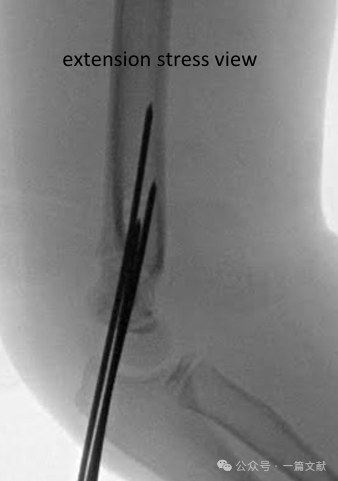

* Type 4: Unstable in both extension and flexion; periosteal sleeve is disrupted.

* Distinguishing Type 3 vs. Type 4: Differentiation is made intraoperatively using fluoroscopy with the patient under anesthesia—this is an intraoperative distinction.

Intraoperative Fluoroscopic Assessment of Stability:

* Consider dynamic fluoroscopic stress views to evaluate the stability of the reduction construct (especially if limited follow-up is planned).

* AP View: Apply rotational stress, varus/valgus stress.

* Lateral View: Assess range of flexion and extension.